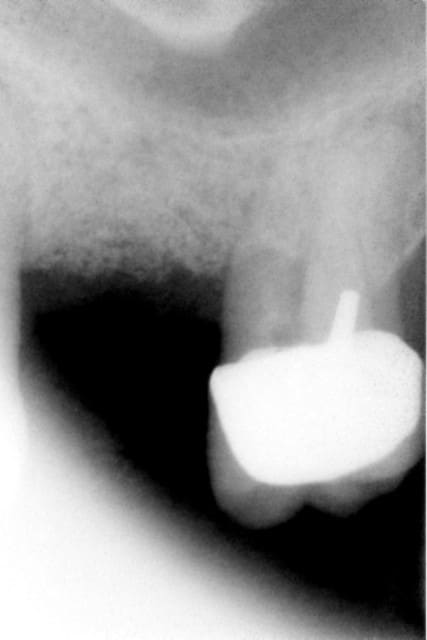

fracture plancher de 16